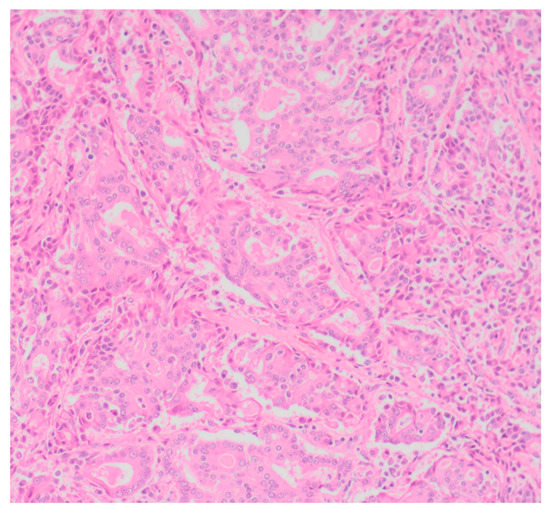

Sixty-five (87.8%) of the tumors examined histologically were classified as malignant, while 9 (12.2%) were classified as benign. All MGTs histologically identified as malignant included at least three cellular or nuclear criteria of malignancy (Figure 1 and Figure 2). Histological evidence of peri-tumoral (n = 6) and lymphatic (n = 4) invasion was identified in 10 malignant tumors, while randomly distributed areas of necrosis within the neoplasm were observed in 16 malignant tumors.

Figure 2. Tubular carcinoma (Grade III), mammary gland, canine (high power). Highly pleomorphic neoplastic cells exhibiting multiple cellular and nuclear criteria of malignancy.